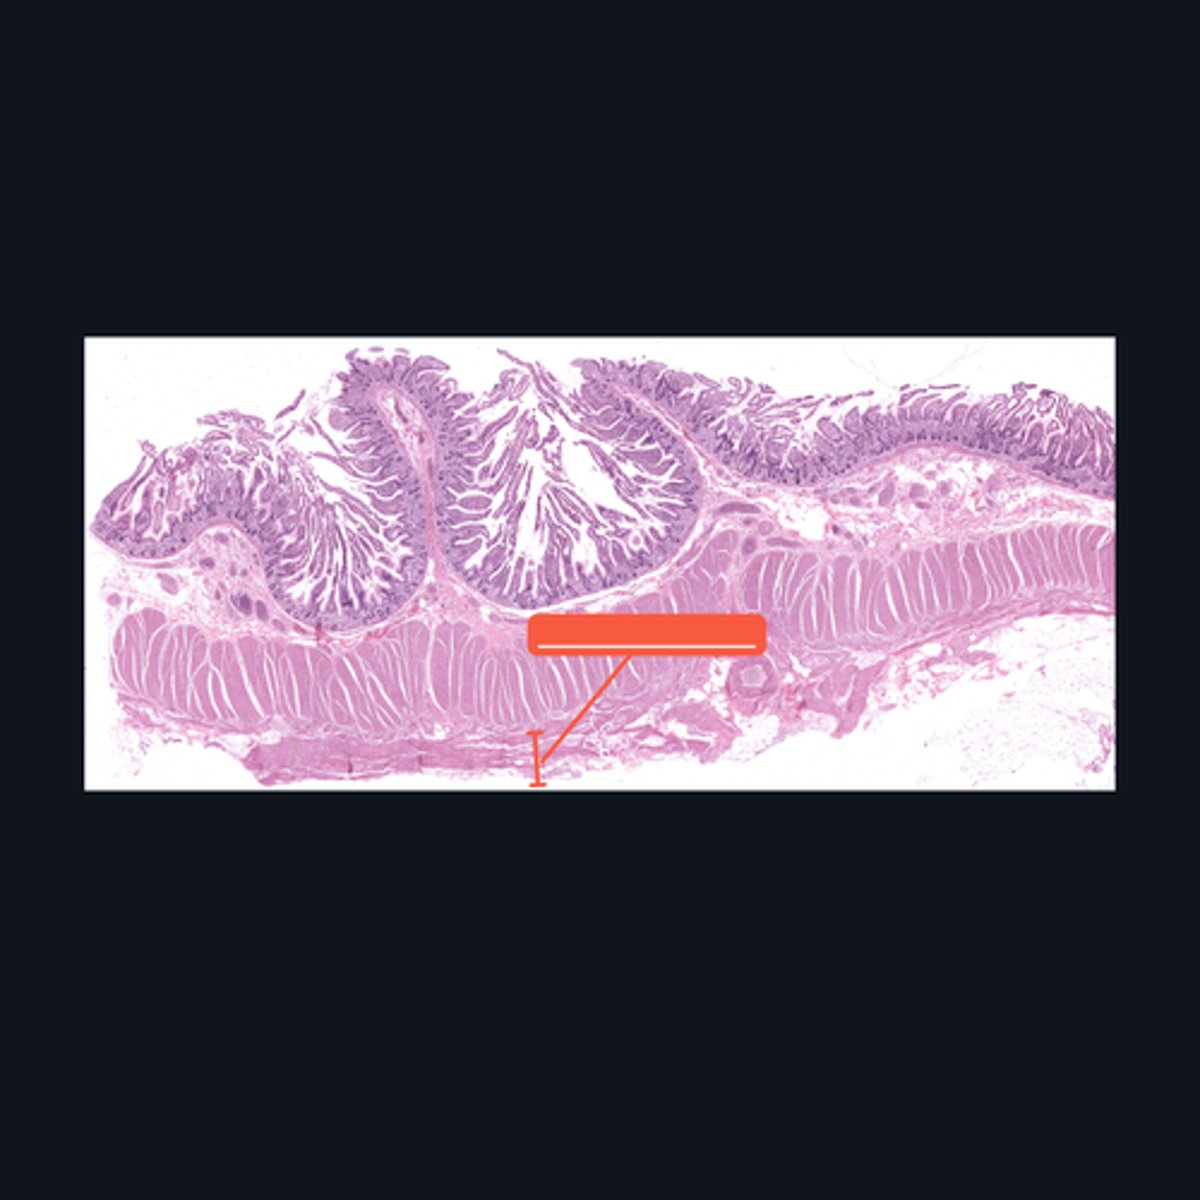

Mucosa, Submucosa, Muscularis Externa

Identify the histologic layers of the digestive tract

Submucosa

Identify the pointed histologic layer of the digestive tract